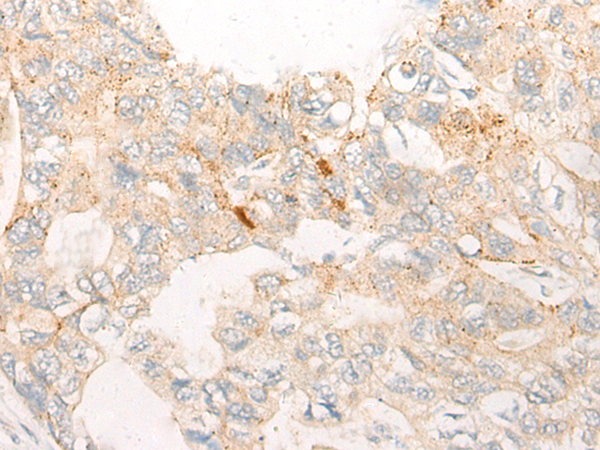

(Immunohistochemistry of paraffin-embedded Human gastric cancer tissue using CHMP2B Polyclonal Antibody at dilution of 1:25(×200))

(Immunohistochemistry of paraffin-embedded Human liver cancer tissue using CHMP2B Polyclonal Antibody at dilution of 1:25(×200))